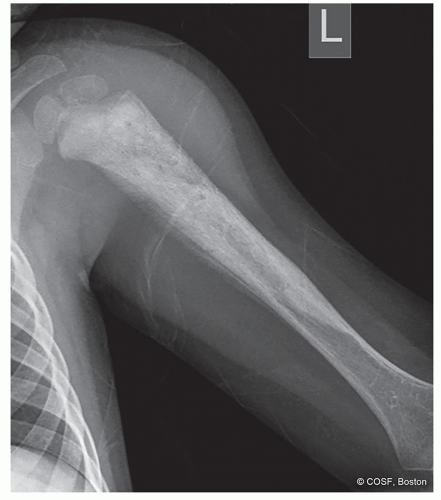

How is the bone responding to the tumor: margination, periosteal reaction? (Figures 41.1,41.2,41.3,41.4,41.5,41.6,41.7,41.8,41.9)

Diaphysis: Ewing sarcoma (see Figure 41.4)

Fibrous dysplasia and Paget disease can involve the entire length of the bone (see Figure 41.6)